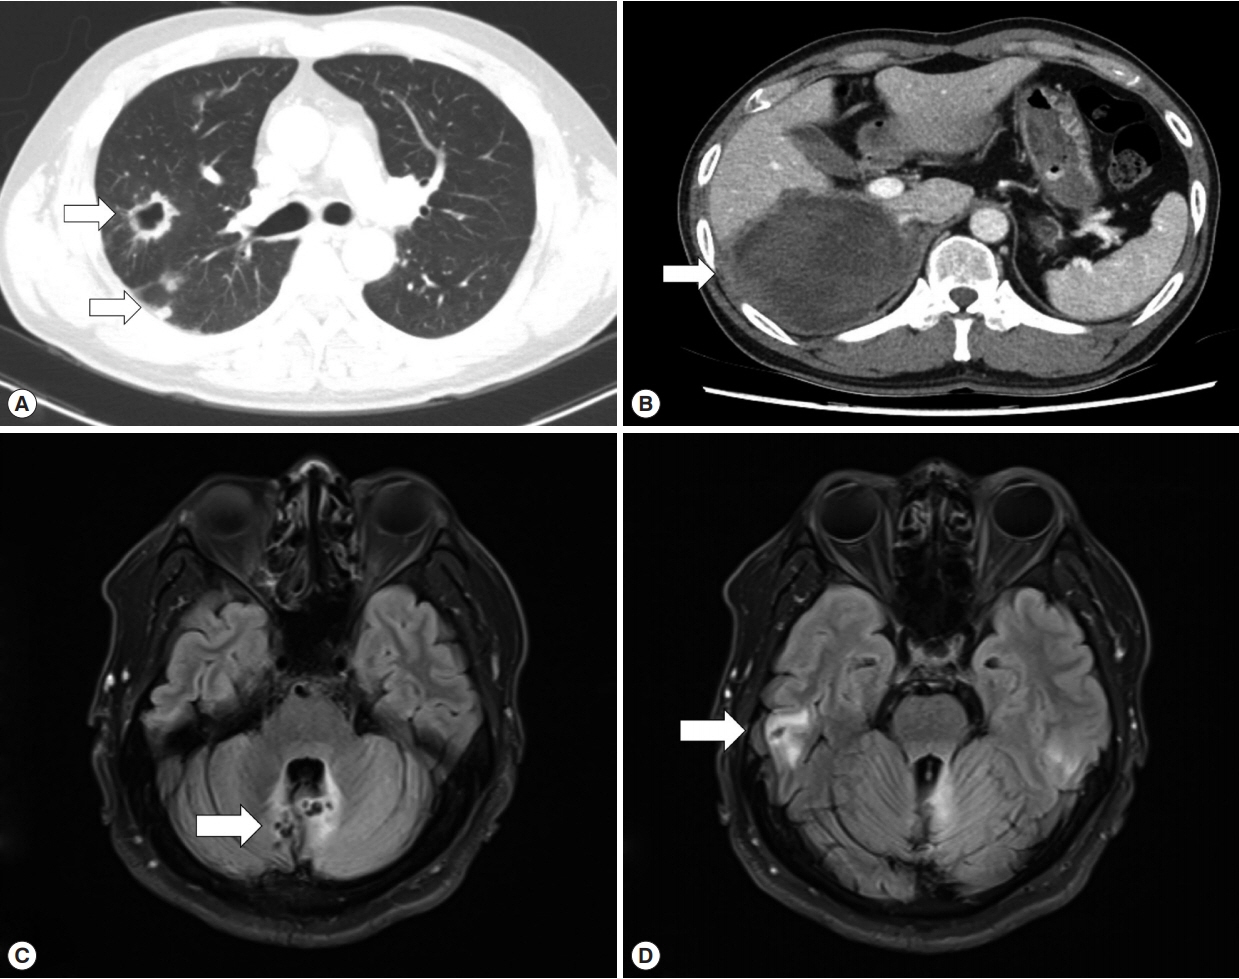

In April 2018, the patient visited another hospital because his dry cough had progressed. CT revealed multiple cystic lesions in both lungs and a 12.4 cm liver cyst involving the right adrenal gland (Fig. 2A, B), and a follow-up brain MRI was performed that showed aggravated cerebellar lesions and a newly developed cystic lesion in the right temporal lobe (Fig. 2C, D). The patient underwent a right lower lobectomy, right hepatectomy, and right adrenalectomy because malignant disease was suspected. However, the histopathologic exams revealed chronic granulomatous inflammation with the degenerated parasitic organism (Fig. 3A–D). Praziquantel 1,200 mg 3 times a day (50 mg/kg/day) was prescribed for 14 days.

Fig. 2

Cystic lesions in the lung, liver, and brain in April 2018. (A) Chest CT showed multiple cystic to nodular lesions (arrows). (B) Liver CT, with portal vein enhancement, showed a 12.4 cm lobulated mass (arrow). (C, D) Brain MRI T2 sequencing showed new cystic lesions in the cerebellum and right temporal lobe (arrow).

Fig. 2 Cystic lesions in the lung, liver, and brain in April 2018. (A) Chest CT showed multiple cystic to nodular lesions (arrows). (B) Liver CT, with portal vein enhancement, showed a 12.4 cm lobulated mass (arrow). (C, D) Brain MRI T2 sequencing showed new cystic lesions in the cerebellum and right temporal lobe (arrow).